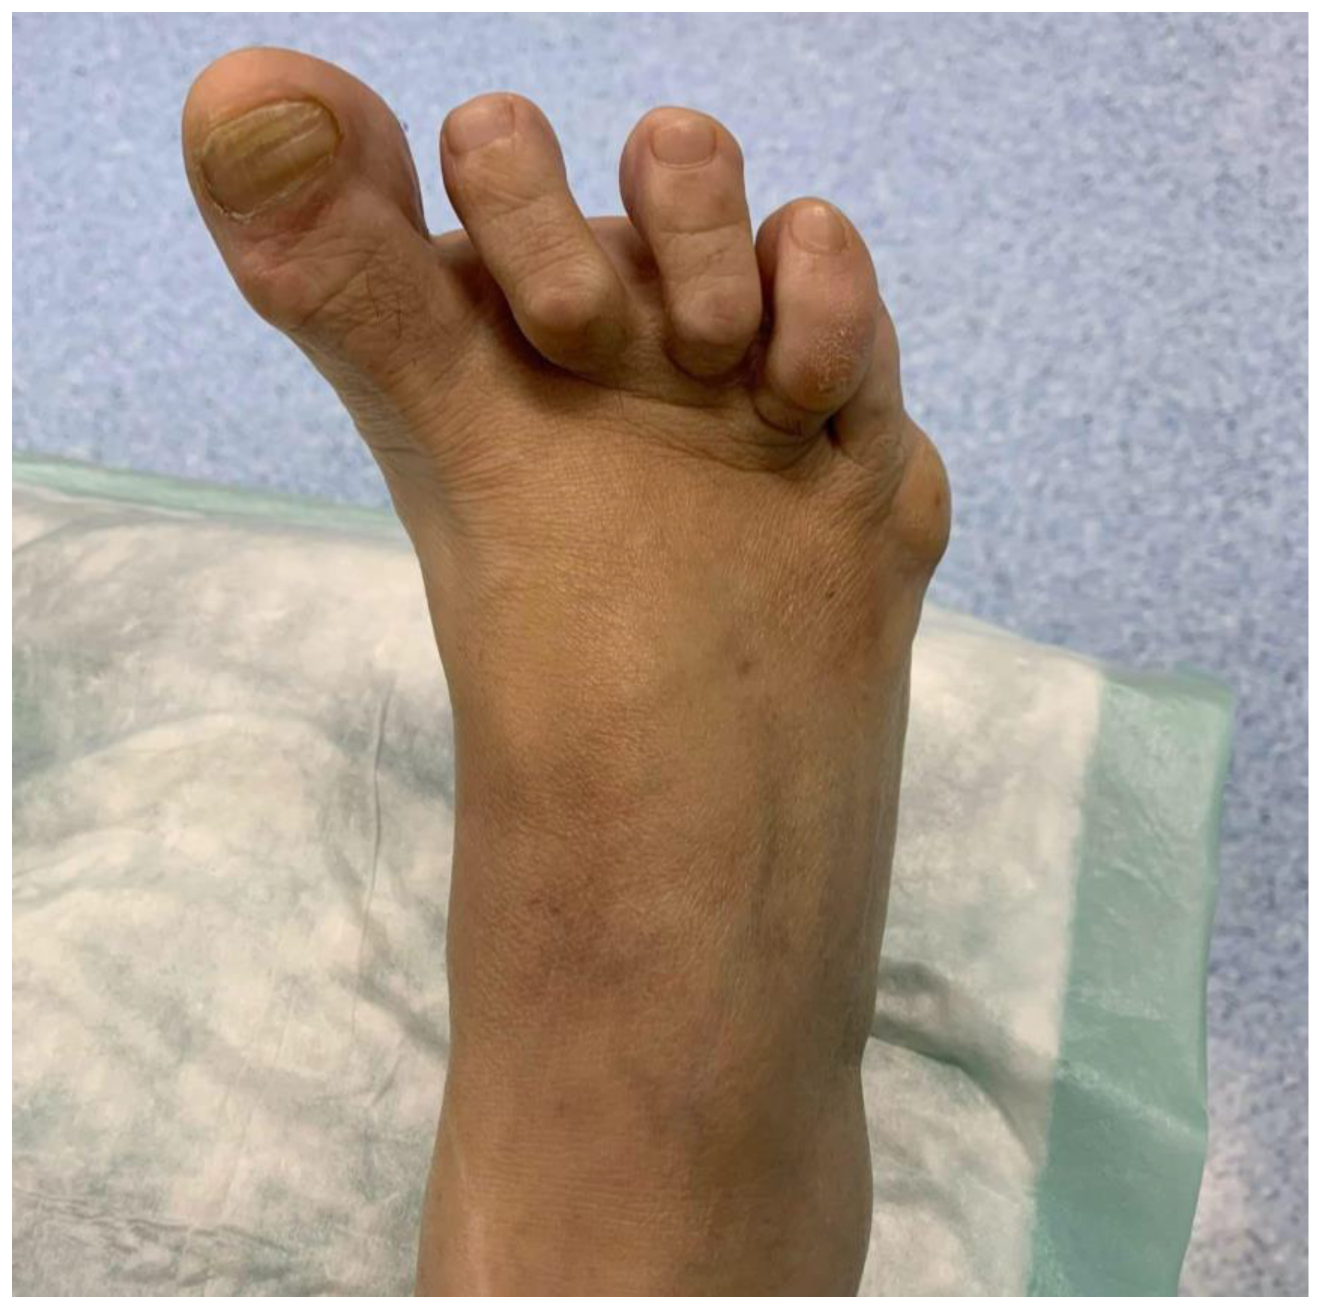

Clinical examination reveals a varus deviation of the first toe and claw position of the lesser toes (Figure 1). Manual reduction of the varus is not possible, and movement of the hallux is painful. In addition, the position of the hallux prevents the patient from putting on shoes normally.

Figure 1. Image of the appearance of the right foot with preoperative hallux varus.

The patient’s clinical presentation included a varus deviation of the hallux and clawing of the lesser toes. This deformity was rigid and painful, further complicating daily activities such as walking and wearing shoes. Radiological studies confirmed severe structural abnormalities, including overcorrection of the first intermetatarsal angle and deformities of the lesser toes [10]. Such findings underscore the importance of preoperative planning and thorough assessment in RA patients, as the risk of surgical complications is inherently higher due to systemic inflammation and reduced bone quality [11]